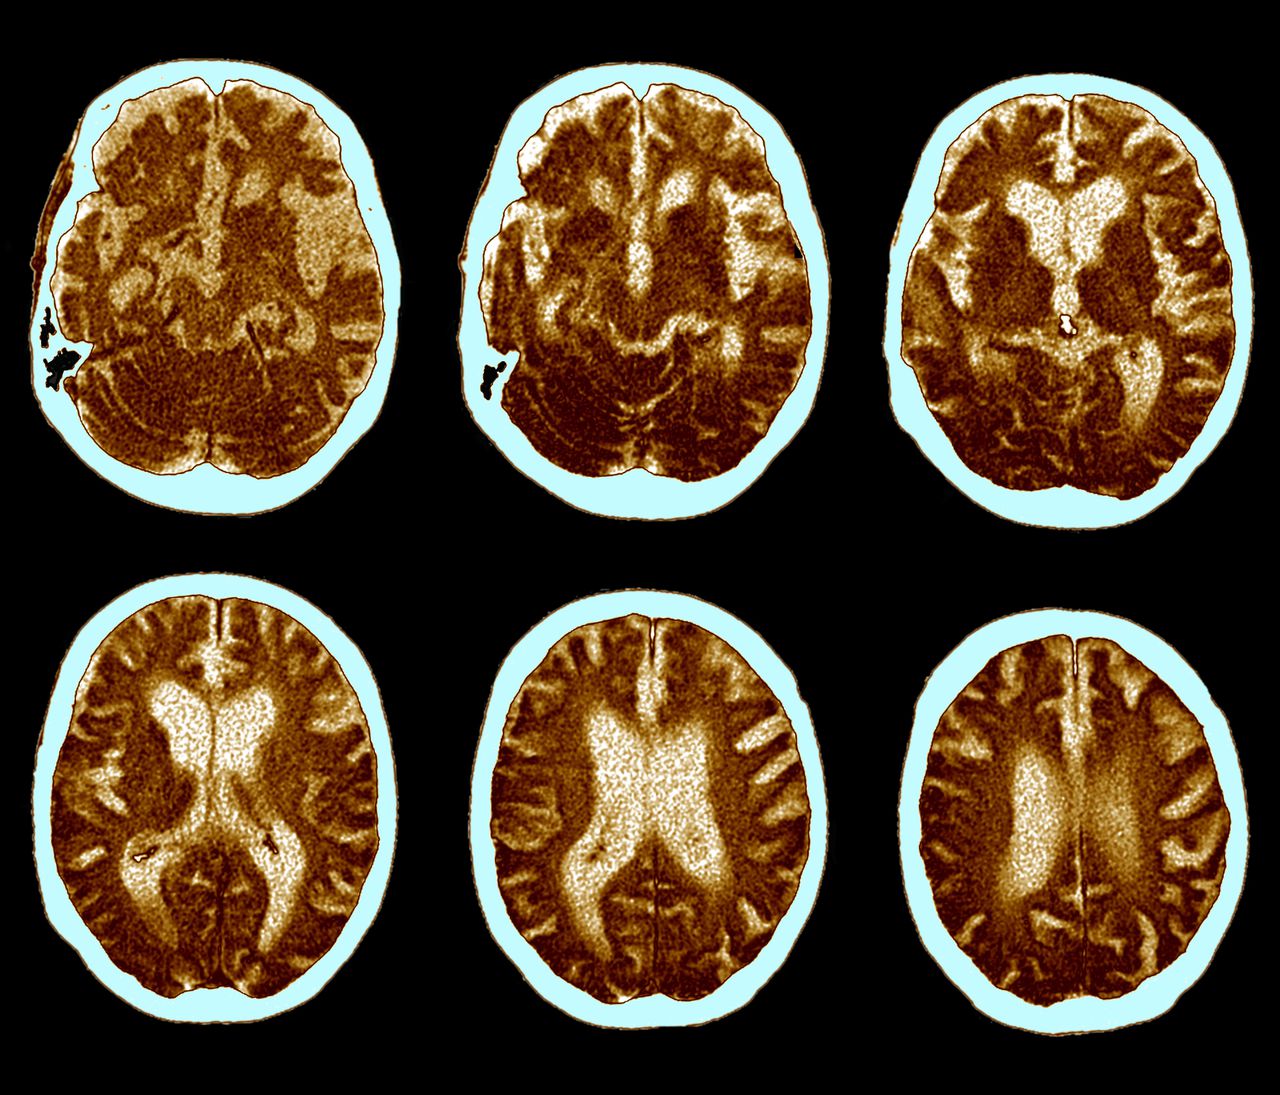

Alzheimer's and Normal Brains, Comparison Stock Image F031/8271 Does Alzheimer's Eat Your Brain Eventually, alzheimer's disease affects most areas of your brain. Healthy eating patterns have been associated with cognitive benefits in studies, but more research is needed — and is underway — to determine if what we eat can prevent or delay. The main way the disease works is to disrupt communication between neurons, the specialized cells that. When amyloid beta clumps. Does Alzheimer's Eat Your Brain.

Normal and Alzheimer Brains, PET Scans Stock Photo Alamy Does Alzheimer's Eat Your Brain Eventually, alzheimer's disease affects most areas of your brain. Healthy eating patterns have been associated with cognitive benefits in studies, but more research is needed — and is underway — to determine if what we eat can prevent or delay. The main way the disease works is to disrupt communication between neurons, the specialized cells that. Here’s what we think. Does Alzheimer's Eat Your Brain.